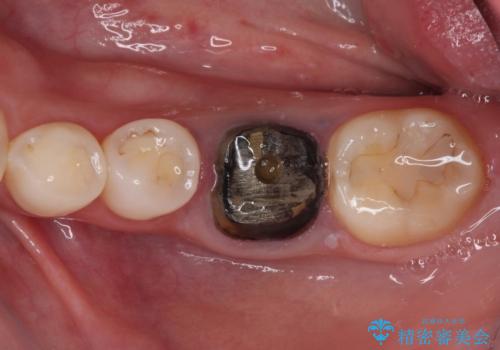

- 奥歯の銀歯が外れたことをきっかけに、全ての銀歯をセラミックに替えたいとのことで来院された患者様です。

第一大臼歯4本と、メタルインレーが装着されている2歯をセラミッククラウンならびにセラミックインレーにて補綴治療・修復治療を行うこととしました。